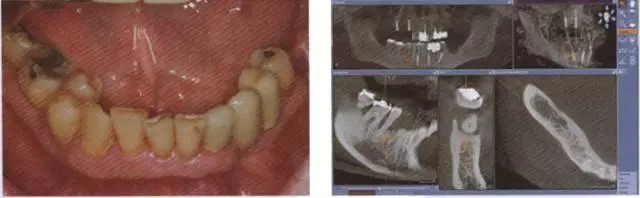

圖8 牙周病破壞了下合的牙齒系統(tǒng)

圖9 對牙周病破壞的下合員牙齒通過 CBCT數(shù)據(jù)進行帶角度的種植規(guī)劃.

圖10 在序列拔牙后及用生理益水中洗之前應(yīng)用光敏劑 (HELB0, bredent medlcal公司).

圖11 在手術(shù)快結(jié)束時放置印模t注用于制作即刻臨時修復(fù)體

圖12 戴入即刻l臨時修復(fù)體。